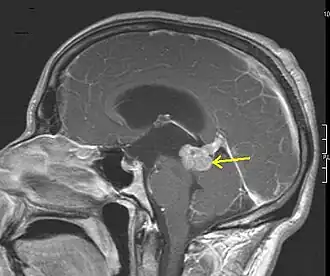

- Standardverfahren ist die Magnetresonanztomographie (MRT), auch Kernspintomographie genannt, ein diagnostisches Schnittbildverfahren zur Darstellung von Organen und Geweben mit Hilfe von Magnetfeldern. Sie basiert auf der Gewebestruktur und dem Wassergehalt und hat eine sehr hohe Erkennungsrate für Hirntumoren, ohne ionisierende Strahlung einzusetzen. Kontrastmittel ist nicht immer erforderlich. Die Magnetresonanzspektroskopie (MRS) ist ein in spezialisierten Zentren verfügbares Zusatzverfahren, um aus tumorverdächtigen Arealen ein Signalspektrum aufzunehmen und damit ihre chemische Zusammensetzung abzuschätzen.